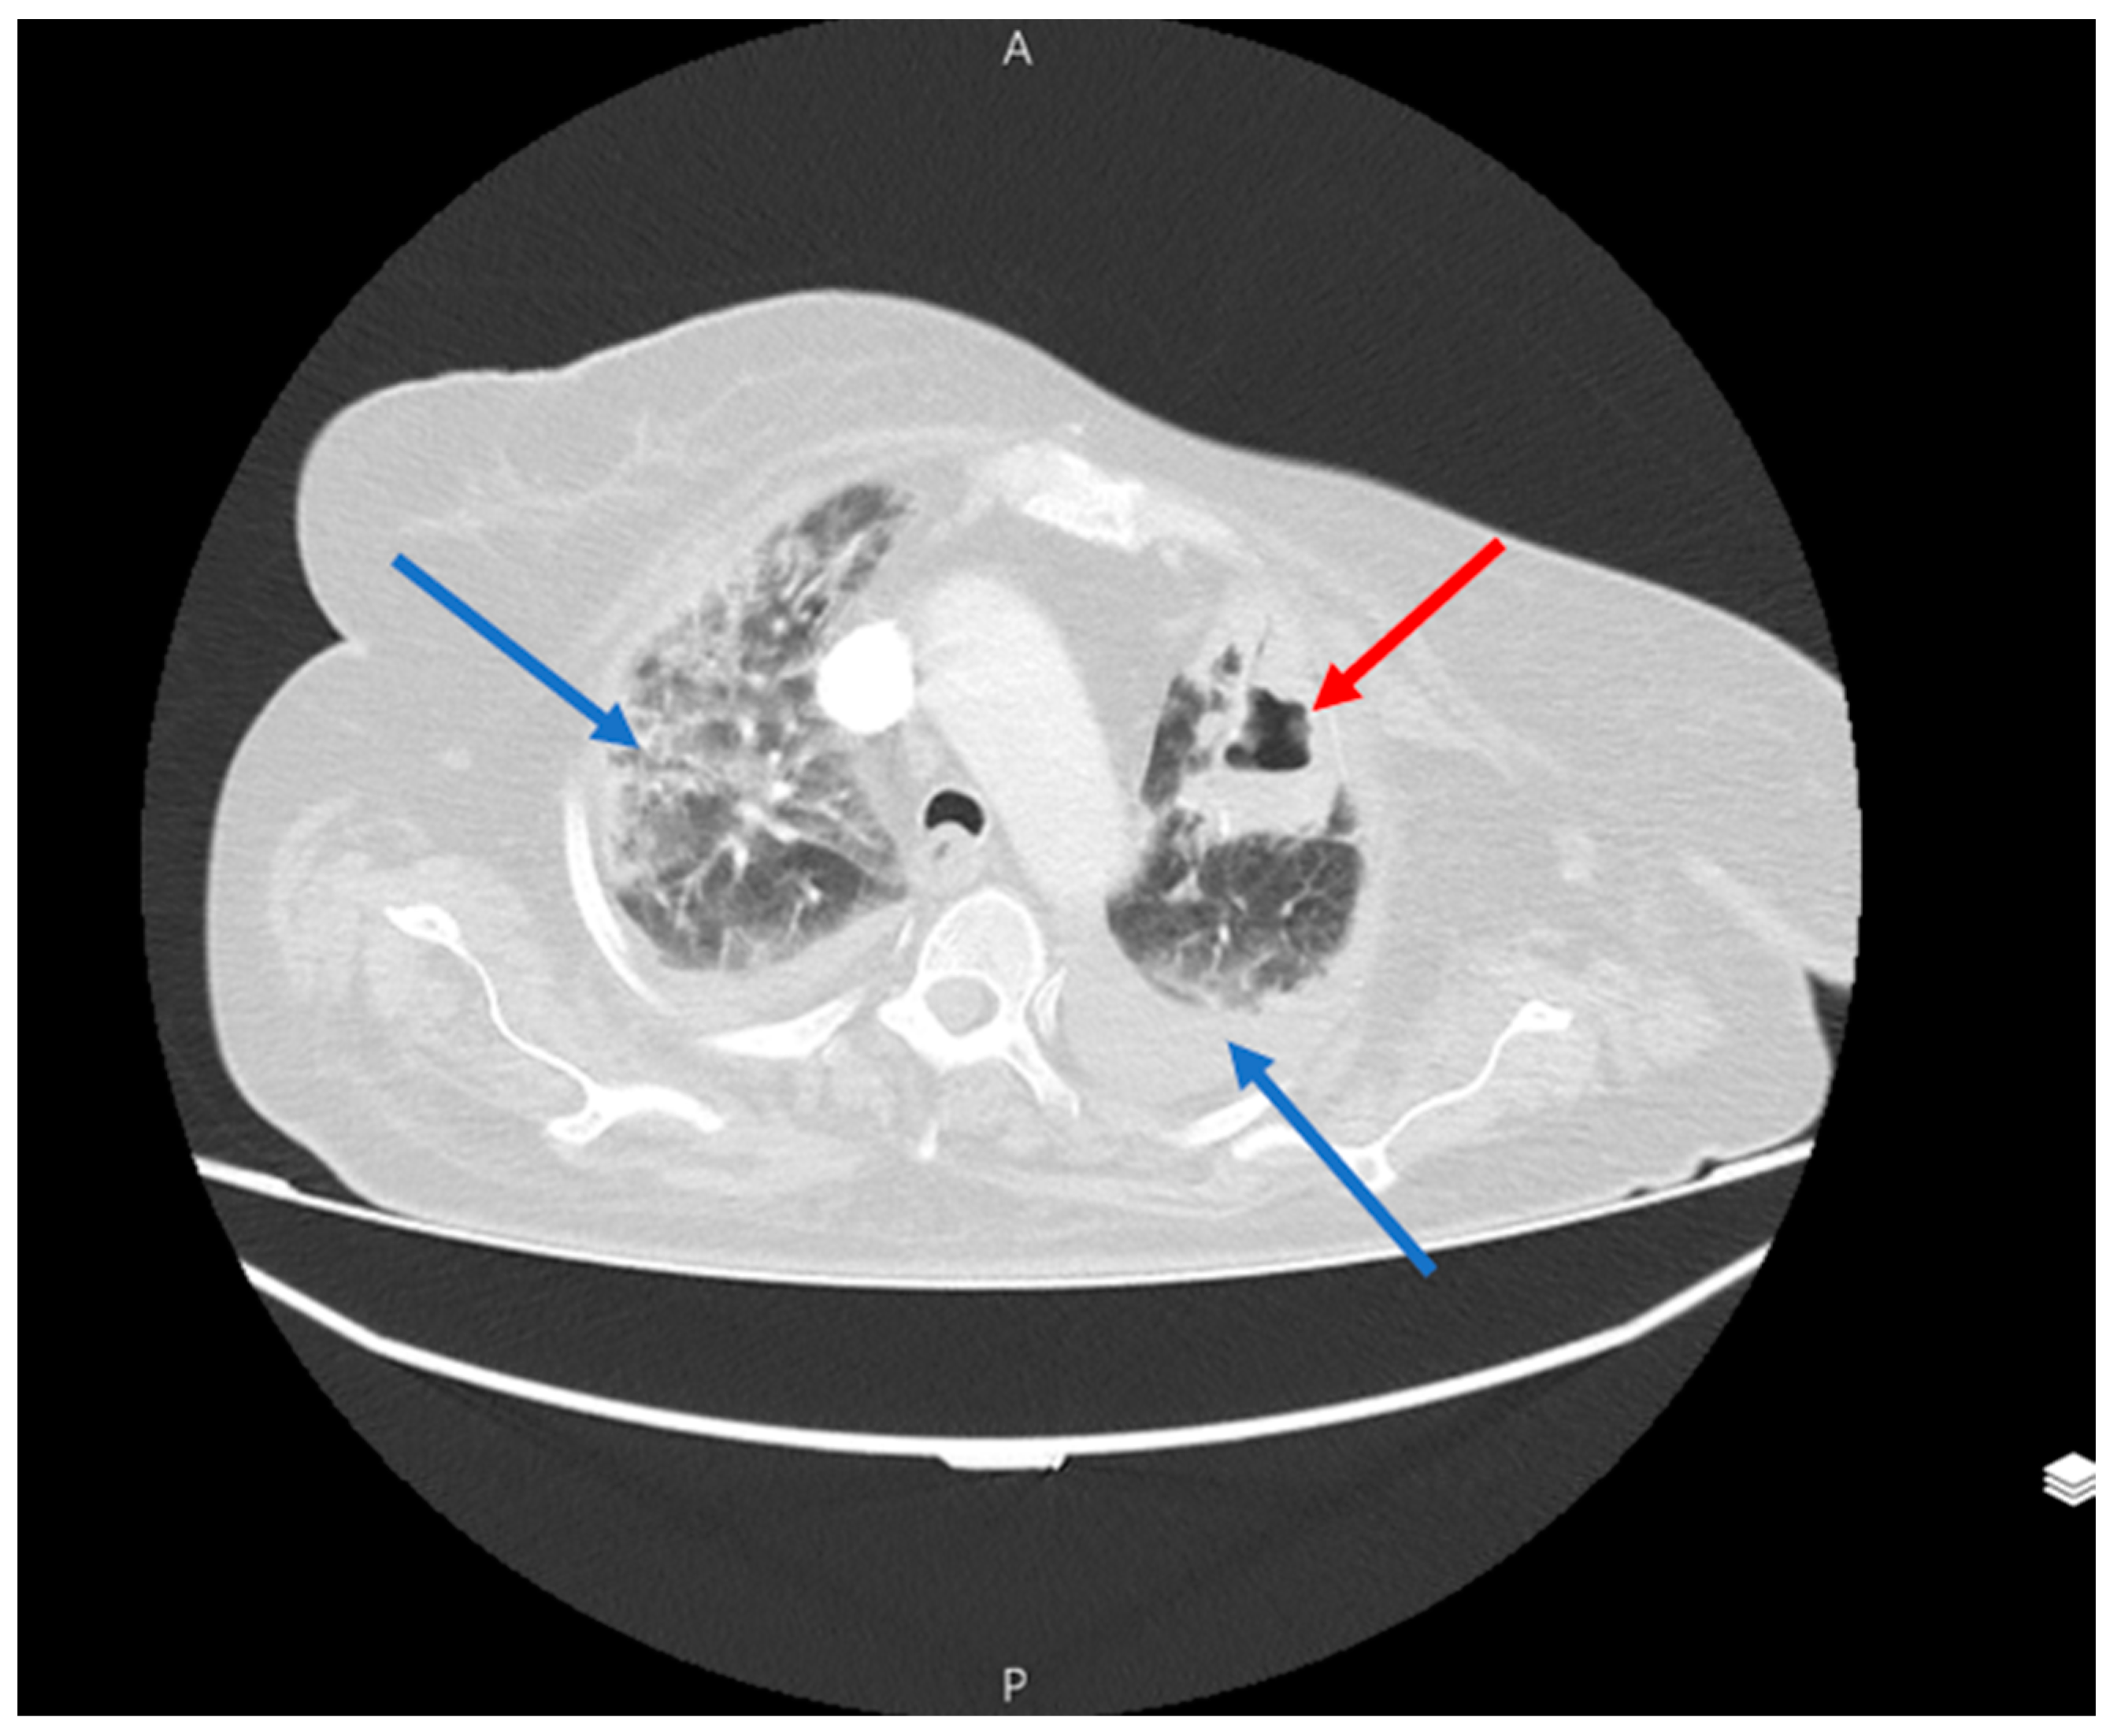

Figure 5.

Right lung pneumothorax (blue arrow) and right lung abscess containing air-fluid level in the RLL (red arrow).

Figure 6.

CT scan of patient 5 days after pneumothorax and removal the chest tube. The lack of abscess shrinkage is noticeable (red arrow).

Figure 7.

An unsuccessful drainage of a lung abscess (red arrow) using a CT scan guide, resulting in a pneumothorax in the right lung and a chest tube insertion after that (blue arrow).